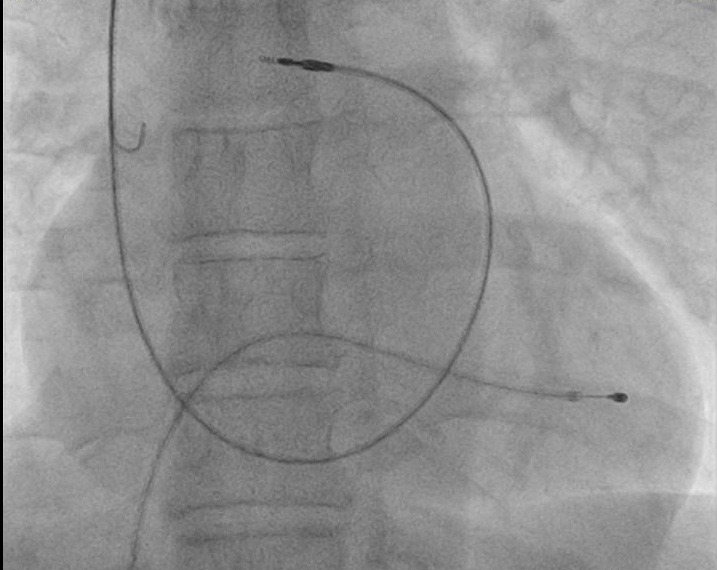

Single versus separate punctures

• In case of difficult punctures

• Routinely ?

• Retained guidewire technique

• Double wire technique